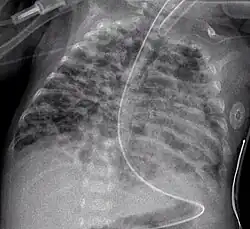

A chest radiograph showing bronchopulmonary dysplasia. -